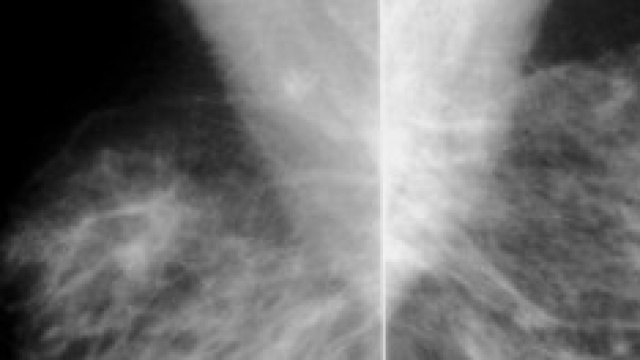

La mammografia è l'indagine radiologica di più comune impiego nella diagnostica senologica che dà informazioni sulla struttura e sulla morfologia della ghiandola. Ha una elevata sensibilità nell'individuazione di lesione mammarie anche di dimensioni millimetriche ancora non palpabili né documentabili con altri esami diagnostici.

Le proiezioni standard eseguite durante un esame di mammografia sono tre: proiezione cranio-caudale, proiezione obliqua medio-laterale e proiezione latero laterale. La compressione della mammella è necessaria per ottenere un buon contrasto di immagine e l'esame è sempre bilaterale e comparativo.

A seconda dell'età, gli aspetti mammografici della mammella cambiano. Gli elementi strutturali di una mammella normale in età fertile sono tre: tessuto adiposo, parenchima ghiandolare e tessuto connettivo mammario. La densità radiologica della ghiandola mammaria si riduce in maniera significativa con l'avanzare e dell'età: con l'insorgere della menopausa, si determina una diminuzione degli elementi stromali ed una loro sostituzione con tessuto adiposo.

La relativa abbondanza delle tre componenti strutturali determina la densità della mammella.